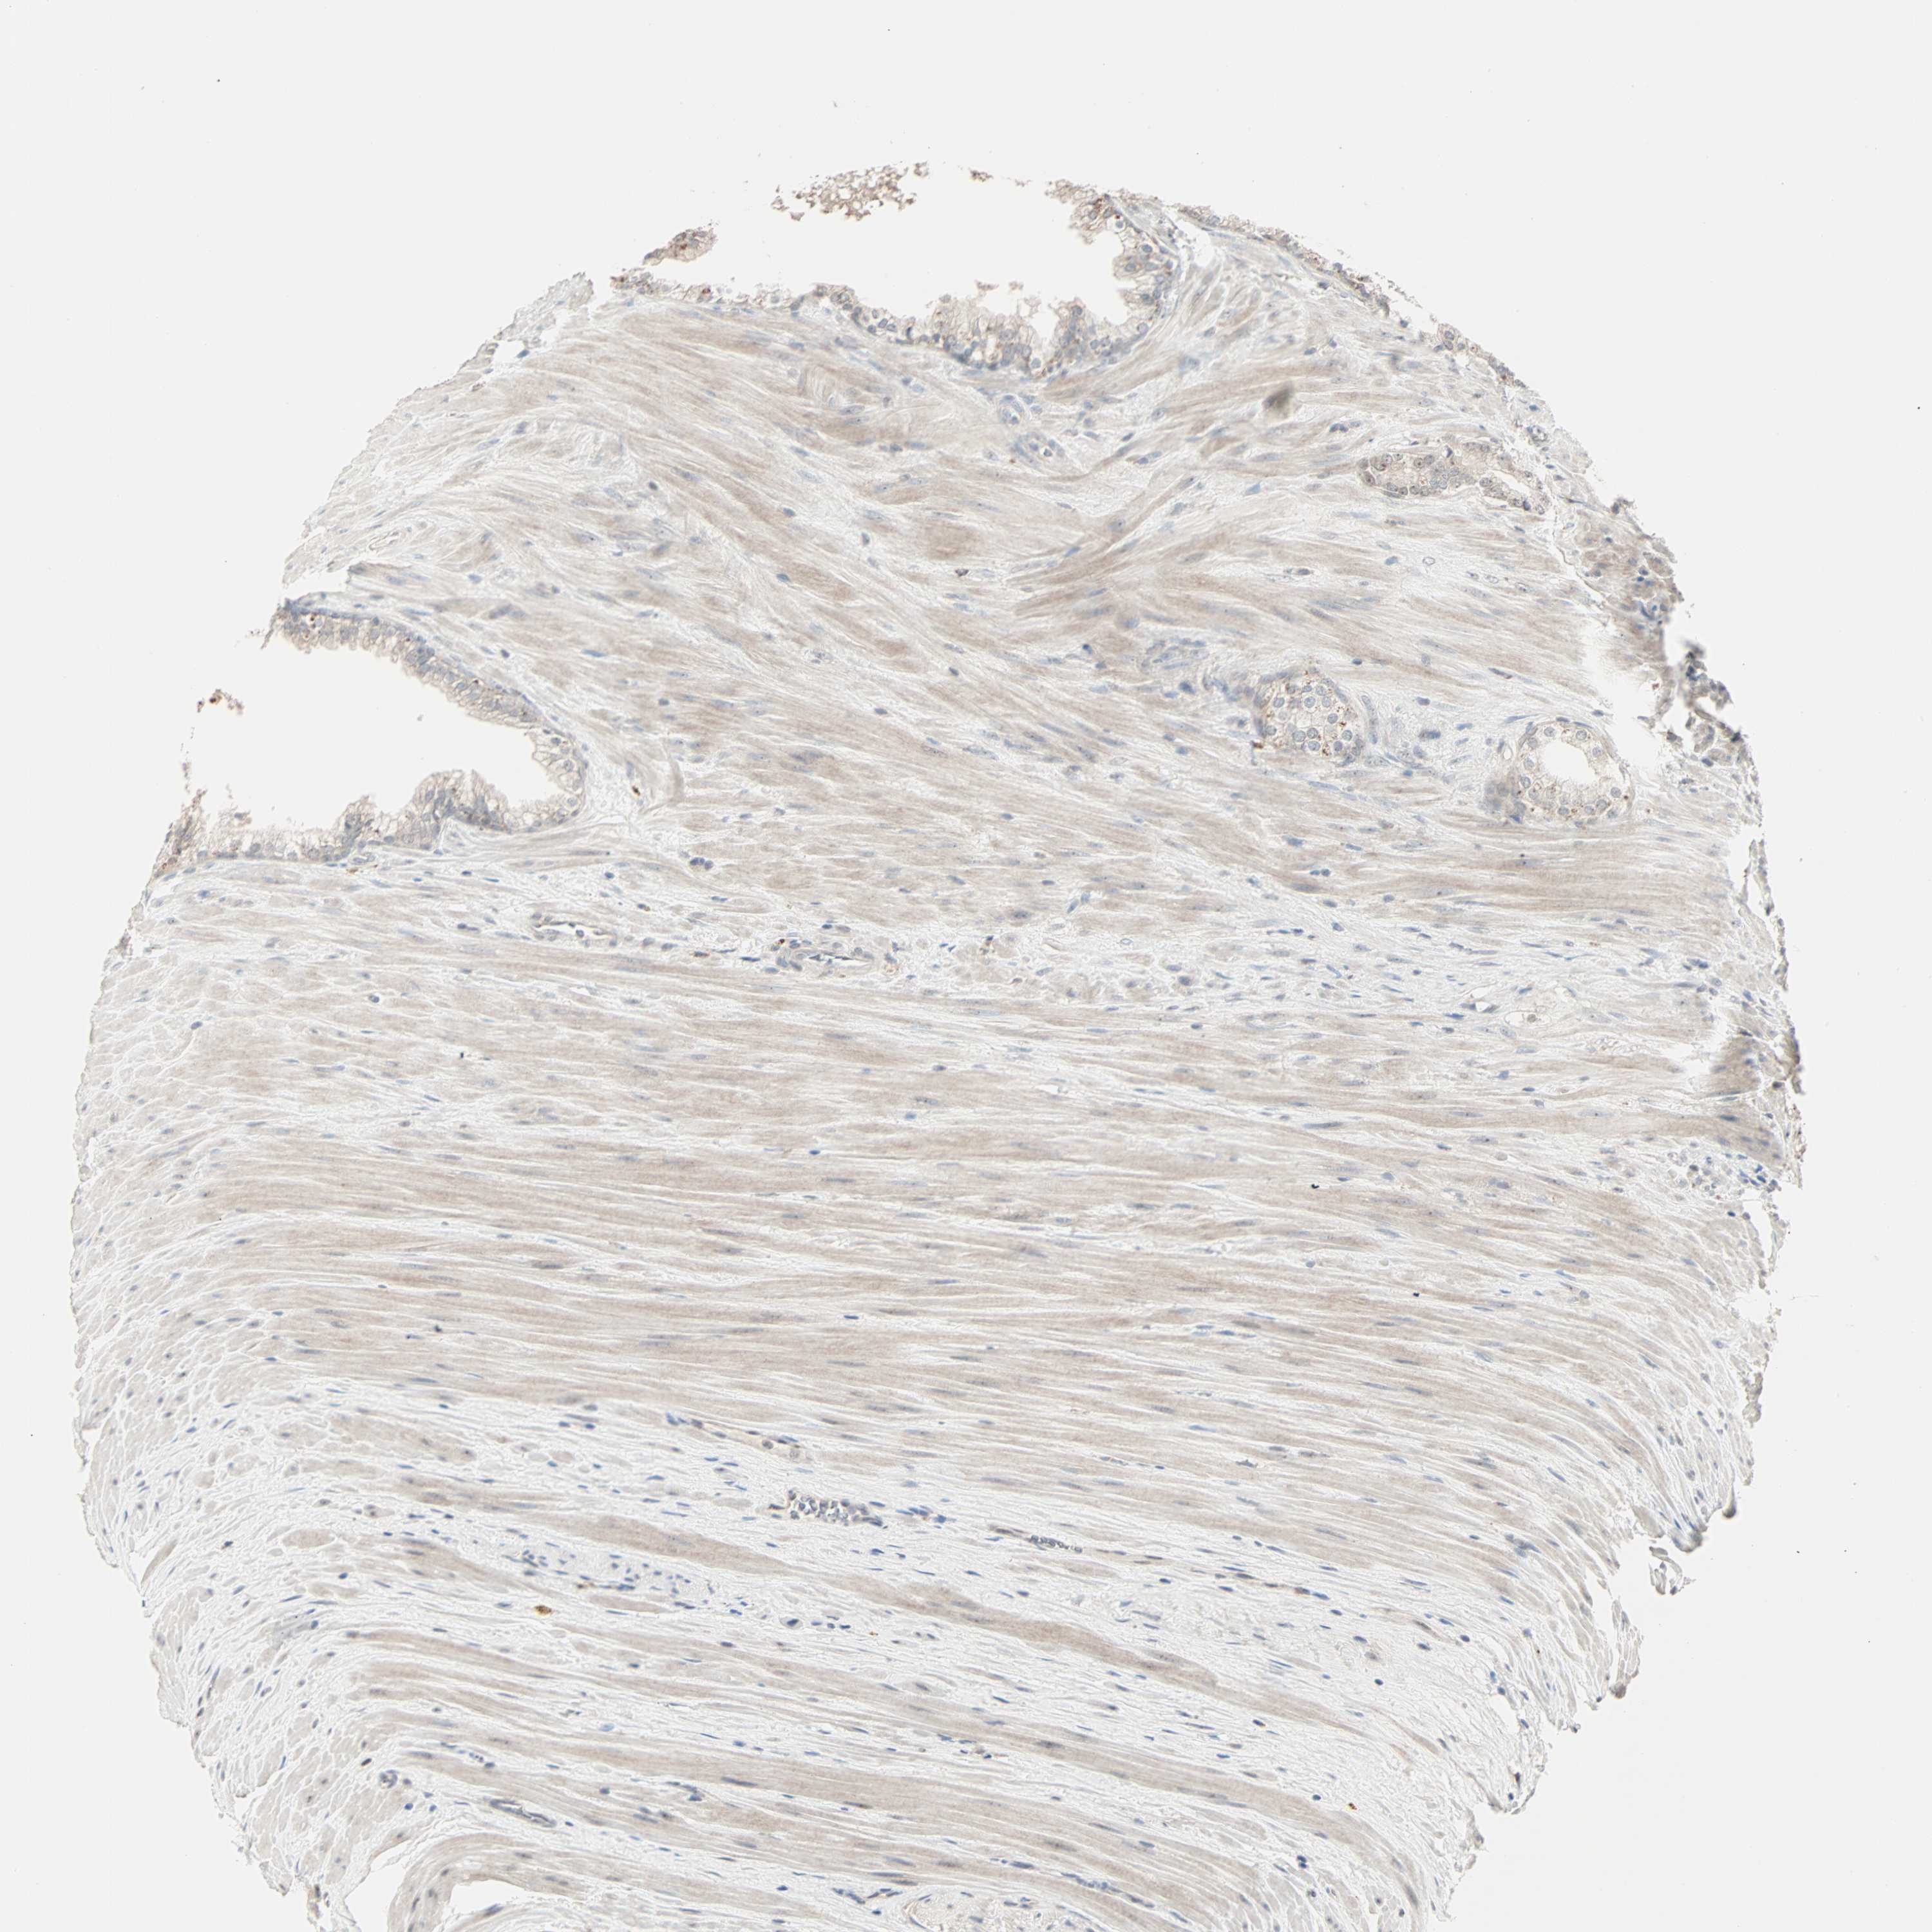

PROSTATE CANCER - Protein expressioni

A mouse-over function shows sample information and annotation data. Click on an image to view it in a full screen mode. Samples can be filtered based on level of antibody staining by selecting one or several of the following categories: high, medium, low and not detected. The assay and annotation is described here.

Antibody stainingi

Antibody staining in the annotated cell types in the current human tissue is reported as not detected, low, medium, or high, based on conventional immunohistochemistry profiling in selected tissues. This score is based on the combination of the staining intensity and fraction of stained cells.

Each image is clickable and will lead to virtual microscopy that enables deeper exploration of all samples and also displays staining intensity scores, fraction scores and subcellular localization as well as patient and tissue information for each sample.

Antibody HPA007610

Staining

High

Medium

Low

Not detected

Intensity

Strong

Moderate

Weak

Negative

Quantity

>75%

75%-25%

<25%

None

Location

Nuclear

Cytoplasmic/membranous

Cytoplasmic/membranous,nuclear

Adenocarcinoma, Low grade

Adenocarcinoma, High grade